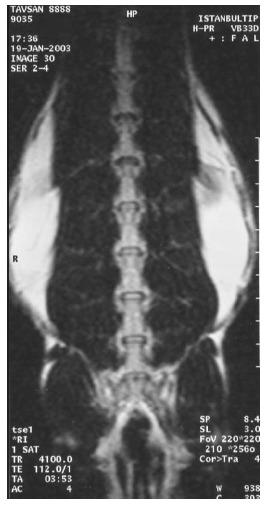

At the first MRI's, we observed that intervertebral discs and vertebral bodies of all the rabbits were healthy (Fig. 7). After the degeneration of intervertebral discs, the degenerated T12-L1 and L1-L2 discs of all the rabbits displayed a collapsed appearance, at the second MRI (Fig. 8). At the third MRI examination, which was made after the fibroblast injection, no radiological recovery of degenerated intervertebral discs could be observed (Fig. 9).

Fig. (7).

Healthy discs on MRI.

Fig. (8).

Degenerated discs on MRI.

Fig. (9).

Discs after fibroblast injection on MRI.